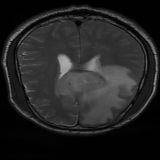

We obtain a subject-wise mean Dice score of 32.94% without any post-processing. By using a simple post-processing with erosion and dilation with filters, this number improves to 48.20% mean Dice score. In comparison, a similar study conducted by [3] consisting of a multitude of algorithms including AnoVAEGAN [4] and f-AnoGANS, obtained a best mean score of 27.8% Dice after post-processing by f-AnoGANS. Before post-processing the best method was Constrained AutoEncoder [8] with a score of 9.7% Dice. An exhaustive list is presented in Table 1. Figure 4 shows sample images of our results.

We obtain a subject-wise mean Dice score of 63.67% for the brain tumor segmentation. Utilizing a simple post-processing scheme of erosion and dilation with filter, we improve our mean Dice score to 68.01%. Figure 4 shows samples generated by our ASC-Net and Table 2 shows our before and after post-processing results. We attempted to apply f-AnoGANs [34] by following their online instructions and failed to generate good reconstructions as shown in Figure 5. The failure of AnoGANs in the reconstruction brings to light the issue with the regeneration based methods and the complexity and stability of GAN-based image reconstruction.

We obtain a slice-wise mean Dice score of 32.24% for this liver lesion segmentation, which improves to 50.23% by using a simple post processing scheme of erosion and dilation with filter. Sampled results are shown in Fig. 4. Compared with [42], which obtains a mean Dice score of 40.78% and a standard deviation of 0.43%, we improve the mean Dice score by almost 10%, but has a much larger standard deviation. Unlike [42], where the network is pre-trained on a artificial tumor dataset, and hence the pipeline customized for tumor segmentation, our method do not need such information beforehand. We notice that our standard deviation for BraTS dataset is similar to [27]. This is because novelty/anomaly detection algorithms without a pre-defined task would suffer from the co-morbidities issues discussed in Section 5.